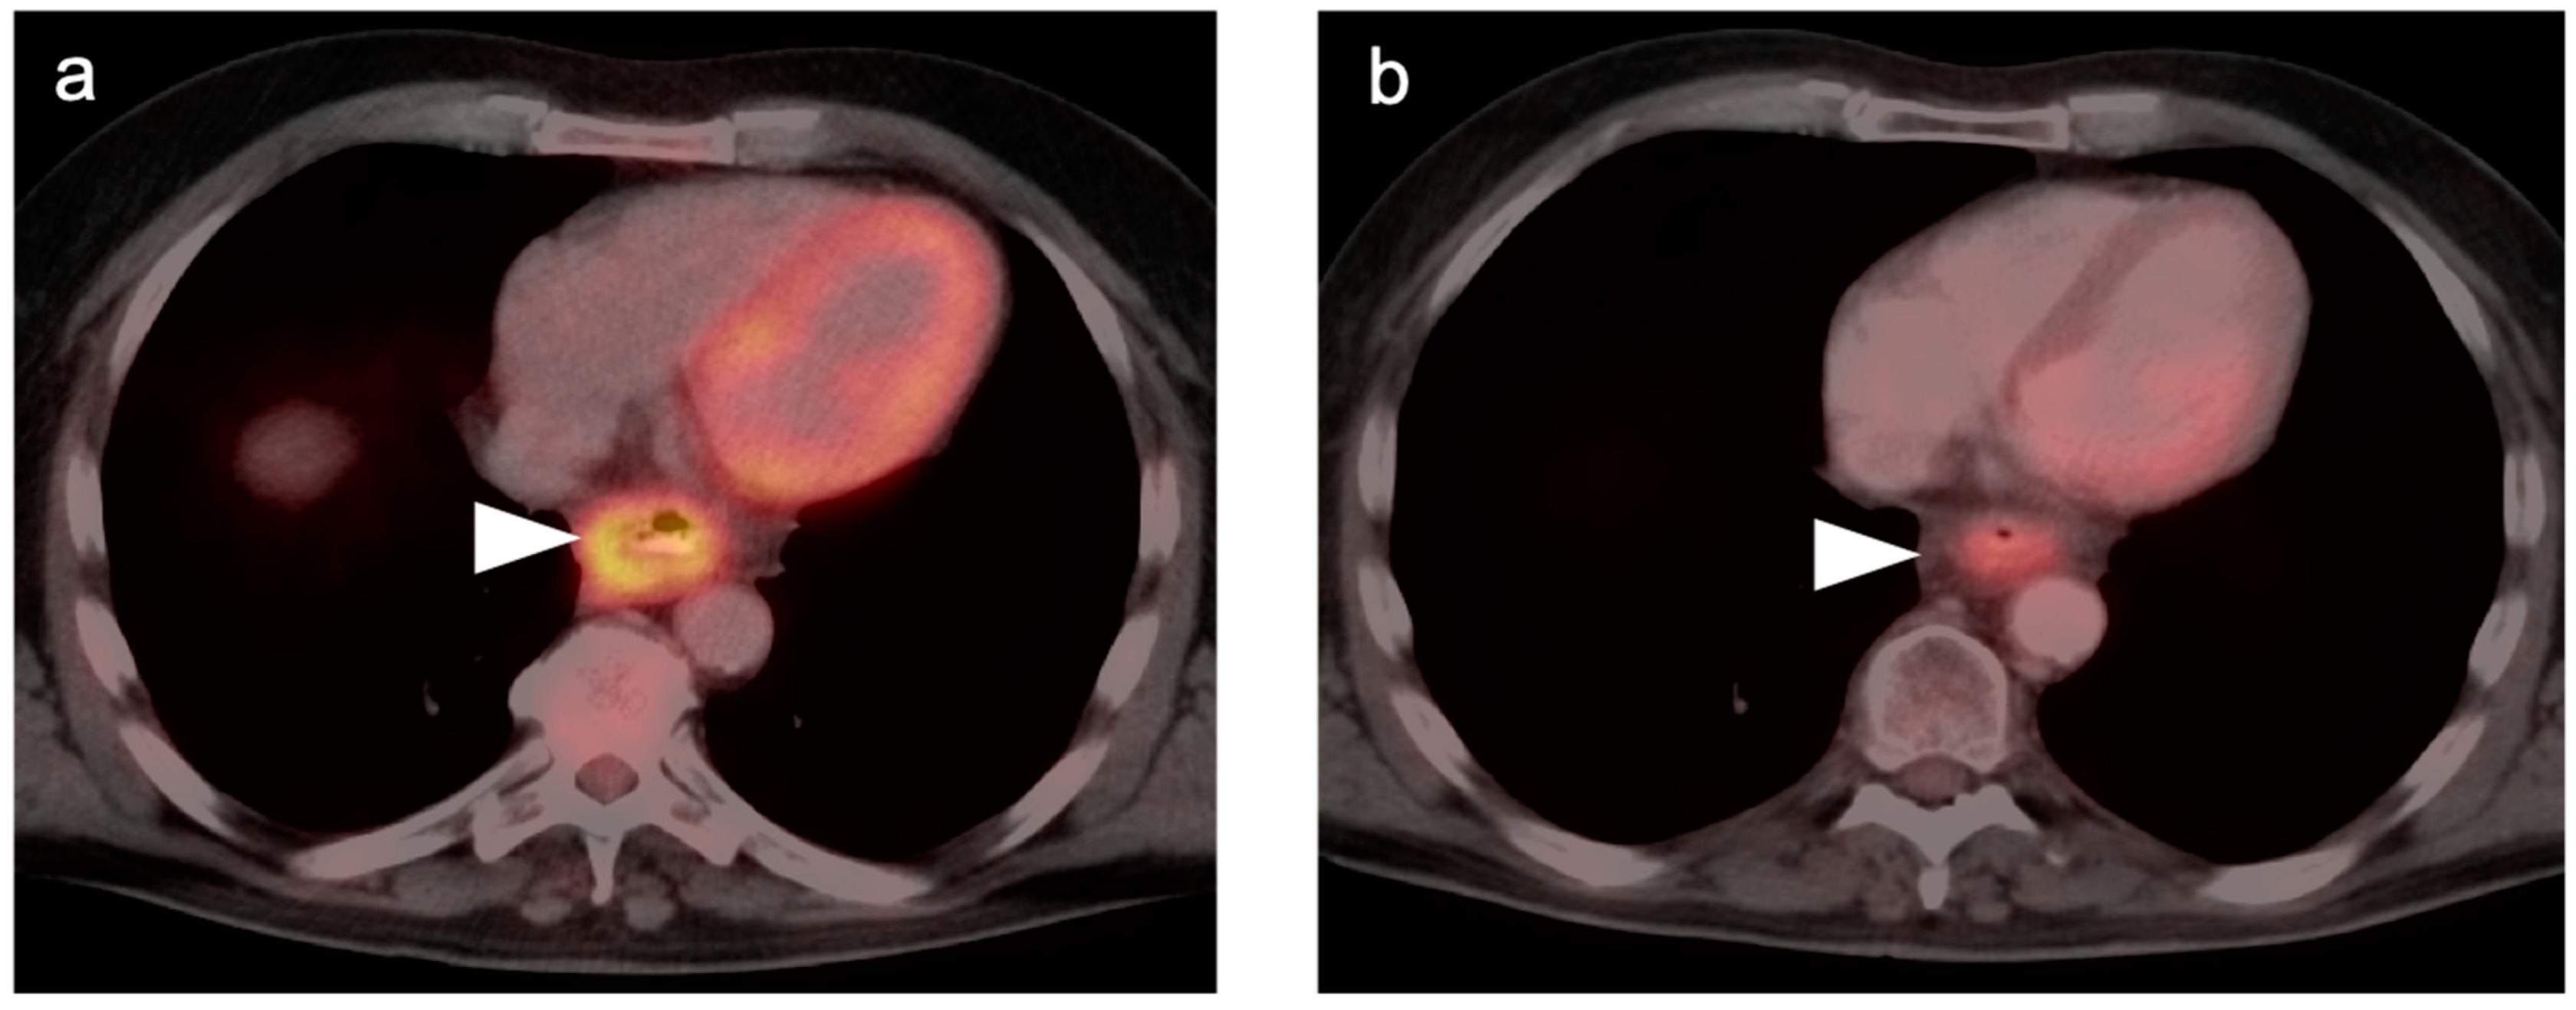

Esophageal and GE Junction Cancer